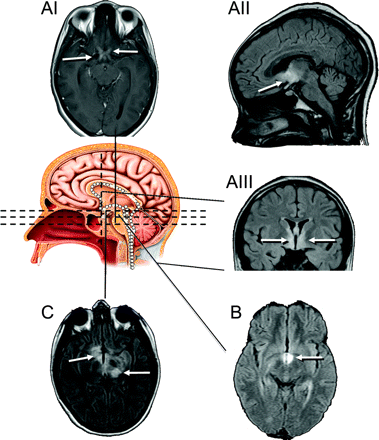

图2代表MRI异常在三个孩子显示视神经交叉谱/间脑的仙女IIIrd心室参与地区已知高度表达aquaporin-4

白色的箭头表示增强,异常的液体衰减反转恢复(天赋),或T2信号。冲黑色线条代表解剖水平关系图。(AI)病人7(12岁的女孩展示与双边视神经炎)增强视神经,交叉,视神经束在T1 (postgadolinium)。天赋异常延伸到下丘脑(暗)和peri-IIIrd心室间脑(哎)。(B)病人3(15岁女孩;另请参阅图1中,C通过我)也出现恶心、抗利尿激素分泌不当综合征,低钠血症(111更易/ L),月经不规则,下丘脑病变(天赋)。188金宝慱官网下载(C)患者6(15岁的男孩;另请参阅图1中,我己经)天赋异常左丘脑和下丘脑。